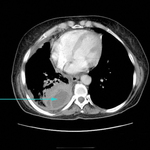

CT scan showing metastatic malignancy of pleura

From the collection of Dr Ami Rubinowitz; used with permission